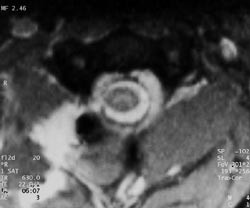

Pasienten falt om og hadde pustebesvær og kunne ikke bevege høyre sides ekstremiteter. Han ble brakt til lokalsykehus og man påviste hemothorax på høyre side, dette ble drenert. Nevrologisk undersøkelse viste høyresidig hemiparalyse og venstresidig bortfall av smerte- og temperatursans under C3-nivå. Vibrasjons- og leddsans ble ikke undersøkt i akuttfasen. Det ble gjort primær lukning av alle sår. Han fikk penicillin profylaktisk. Dagen etter innkomst ble det gjort MR som viste høysignalforandringer i medulla i C1/C2-nivå (fig 1, 2). Fem dager etter skaden var det øverste såret rødt og hovent. Suturene ble fjernet, og det tømte seg et hematom. Antibiotikum ble skiftet fra penicillin til cefotaksim. Pasienten var høyfebril og hadde stigende CRP-verdi. Dyrkingsprøve fra hematomet viste rikelig vekst av Enterobacter, og det ble igjen skiftet antibiotikum fra cefotaksim til imipenem. Ti dager etter skaden observerte man lekkasje av spinalvæske i såret, og etter 12 dager ble han overført til nevrokirugisk avdeling og operert dagen etter. Det ble gjort ny sårrevisjon samt laminektomi på C1 og C2 og duraplastikk. Man fant en fraktur på bakre atlasbue på høyre side. Duralesjonen var 5 mm lang. Videre var det tydelige kontusjonsforandringer i medulla svarende til duraskaden. C2-roten på høyre side var subtotalt overskåret.

Ved stikkskader i ryggmargen kommer nevrologiske utfall vanligvis akutt, men kan også opptre etter timer eller dager (6). Uansett er det viktig at mistanken vekkes selv med beskjedne ytre skader. Lekkasje av cerebrospinalvæske kan komme umiddelbart, men ikke nødvendigvis. Radiologisk diagnostikk er nyttig for å vurdere skadeomfanget. Konvensjonelle bilder samt CT vil avdekke både skjelettskader og eventuelle gjenværende fremmedlegemer. I tillegg vil CT spesielt kunne påvise intraspinal luft som tegn på penetrerende skade (7). CT vil også kunne påvise hematomer og traumatiske prolapser (7). MR gir imidlertid en mer detaljert oversikt over skader i bløtvev og spesielt i medulla (fig 1, 2). Man vil kunne se laserasjoner og skille mellom ødem og hematomer intraspinalt (5, 7). Slik er MR informativt både for terapi og prognose ved denne type skader. Vi vil likevel understreke betydningen av nøyaktig klinisk diagnostikk. Ut fra kliniske funn bør man raskt kunne fastslå skadenivå. I tillegg må man vurdere om andre organer kan være skadet (oesophagus, lunger, store halskar).